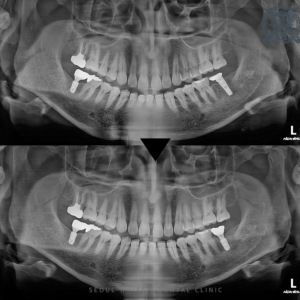

영도치과, 기존 임플란트에 문제가 생겼다면? 재식립 치료 안녕하세요, 영도치과 서울화이트S치과 입니다. 부산쪽 영도치과를 알아보고 내원하시는 분들은 각기 다른 불편함과 고민을 안고 방문해 주십니다. 이 가운데에는 처음으로 임플란트 치료를…